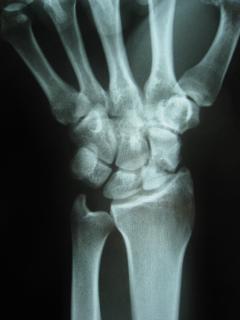

Η ψευδάρθρωση καταγμάτων του σκαφοειδούς δεν είναι σπάνια επιπλοκή (βλ αντίστοιχο κεφάλαιο). Λόγω ανατομικών και φυσιολογικών ιδιαιτεροτήτων του σκαφοειδούς ή λόγω υποτίμησης των ενοχλημάτων εκ μέρους του αρρώστου, το κάταγμα συχνά διαφεύγει της αρχικής διαγνώσεως. Αυτό οδηγεί σε ανεπαρκή αντιμετώπιση, η οποία καταλήγει σε μη πώρωση (ψευδάρθρωση) του σκαφοειδούς. Η κατάσταση αυτή αρχικά έχει ελαφρά ή καθόλου συμπτώματα, με την πάροδο όμως των ετών εγκαθίσταται προοδευτικά επώδυνος περιορισμός της κινητικότητας του καρπού και ελάττωση της δύναμης δραγμού (αδύναμο σφίξιμο σε γροθιά).

Οσο κοντύτερα προς τον αγκώνα είναι το κάταγμα (κατάγματα του κεντρικού πόλου) τόσο μεγαλύτερη είναι η πιθανότητα να εμφανισθεί και νέκρωση του κεντρικού πόλου λόγω διακοπής της αιμάτωσης (άσηπτη νέκρωση). Αυτό καθιστά ακόμη πιο δύσκολη τον χειρισμό της ψευδάρθρωσης.

Προεγχειρητικά

Περίπτωση 2: Προεγχειρητικά